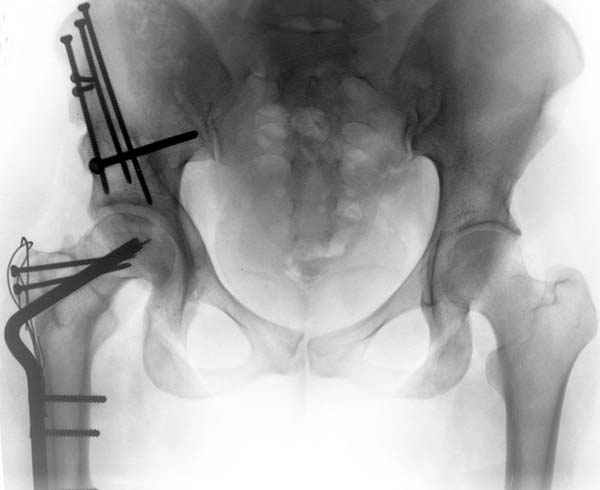

послеоперационные, с учетом биомеханики

сустава #11

№ 11-12 послеоперационные, с учетом биомеханики

сустава